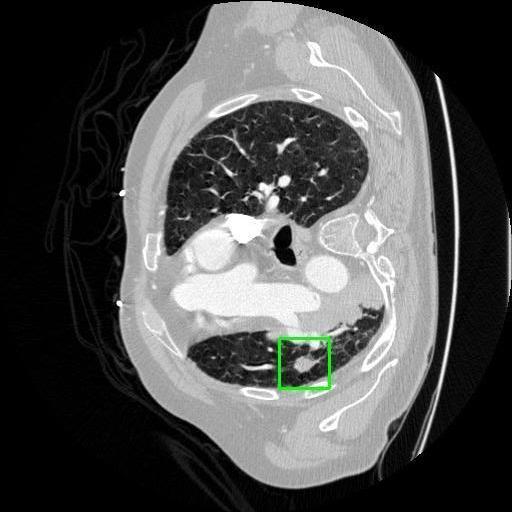

We developed an AI-based system using deep learning models for analyzing lung CT scans to detect and classify pulmonary nodules. We chose the YOLOv11 architecture for its enhanced object detection capability and adapted it specifically for medical imaging, incorporating pixel-level precision and severity classification.

Classification into three severity levels with colored bounding boxes.

Successfully built and deployed an AI model (YOLOv11) capable of detecting lung nodules in CT scans with high accuracy and real-time performance.

Achieved ~0.90 mAP@0.5 on validation data, showing strong object detection capabilities even on complex medical images.

Designed a severity classification system that categorizes nodules into null, moderate, and severe using colored bounding boxes, assisting in rapid clinical decision-making.